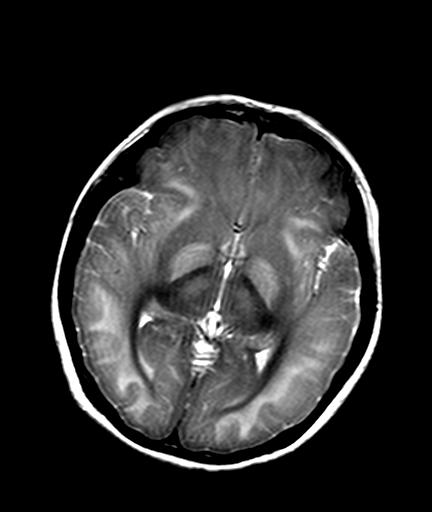

发热、头痛伴精神异常1周

较对称性脑白质异常信号,深部白质t2明显低信号(铁质沉积过多?)

考虑脑白质病变,请结合临床病史及实验室检查进一步分析。

f 23岁